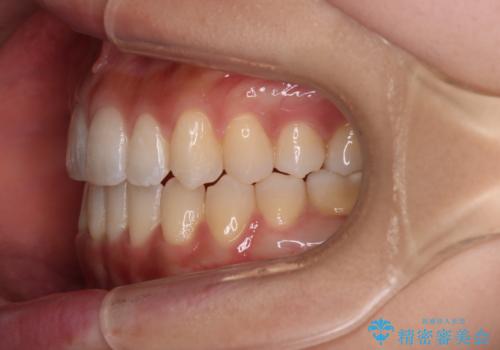

【審美装置】八重歯気になる

- 八重歯と叢生を主訴に来院されました。なるべく健康な歯を残したいという患者様の希望から、右側上下4番抜歯をしてワイヤー矯正する治療計画を立てました。

なるべく健康な歯を残したいという患者様の希望から、右側上下4番抜歯をして矯正しました。片側抜歯だったため、正中がズレないように気をつけながら治療を行いました。

正中もズレることなく主訴である八重歯と叢生を改善することができました。